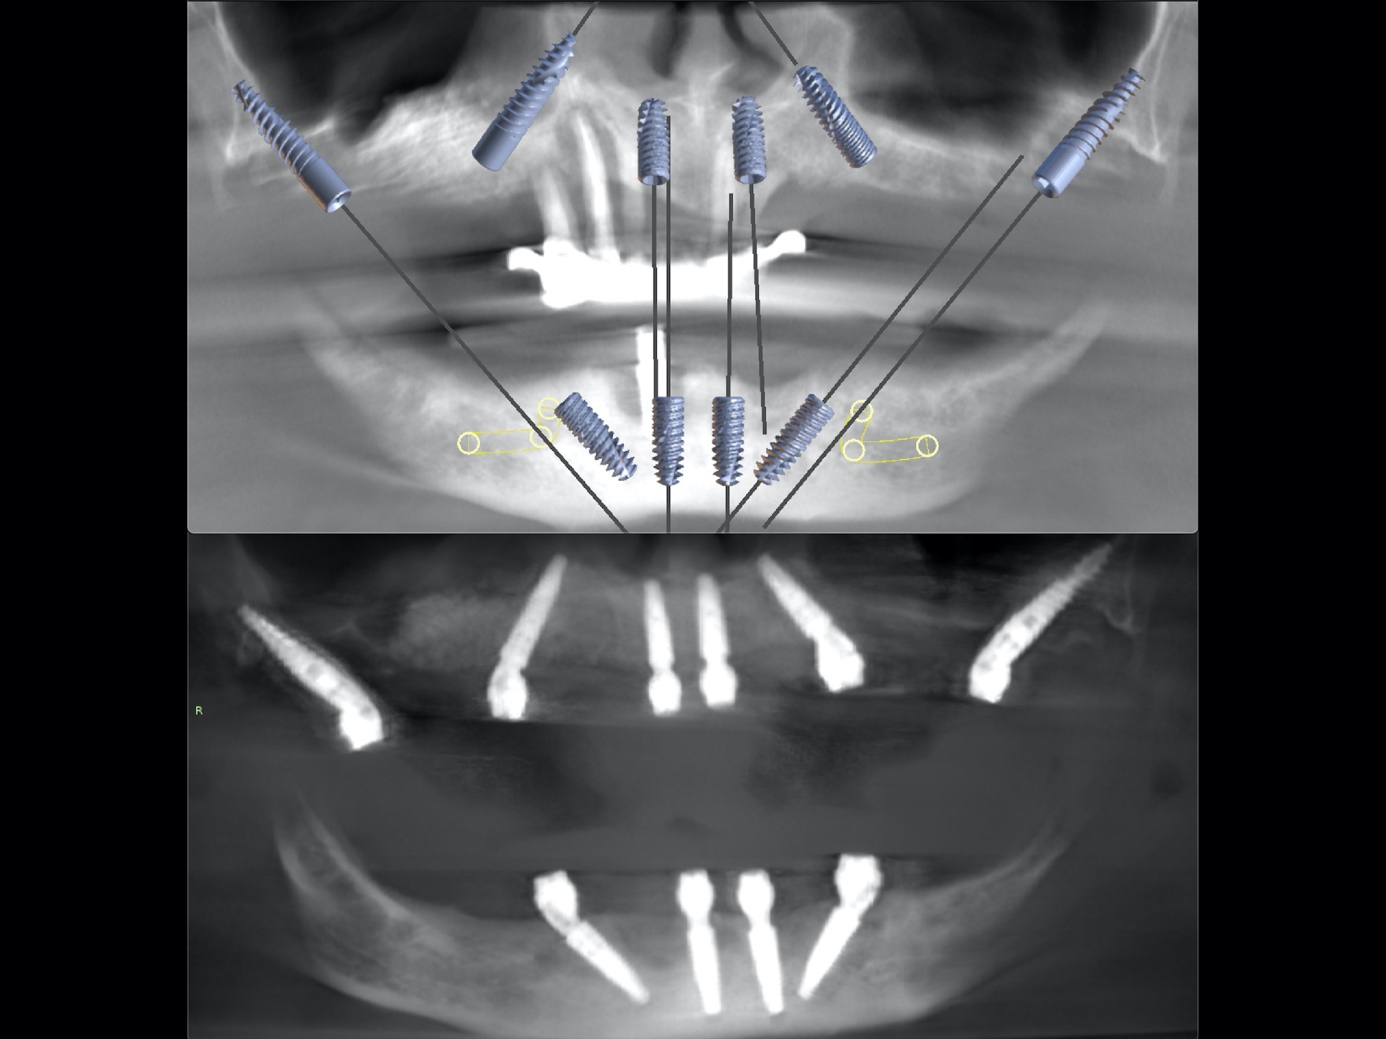

W wydarzeniu wzięli udział chirurdzy szczękowo-twarzowi i chirurdzy stomatologiczni, a także studenci Warszawskiego Uniwersytetu Medycznego zrzeszeni w kole naukowym przy Oddziale Chirurgii Szczękowo-Twarzowej. Uczestnicy mieli okazję obserwować i aktywnie uczestniczyć w kompleksowym leczeniu 74-letniej pacjentki cierpiącej na zaawansowaną periodontopatię, która doprowadziła do całkowitej utraty uzębienia. Zabieg poprzedziło precyzyjne planowanie z wykorzystaniem tomografii komputerowej oraz cyfrowego projektowania uśmiechu na podstawie dokumentacji fotograficznej. Odbudowa protetyczna została wykonana przy użyciu nowoczesnych narzędzi cyfrowych, takich jak skaner wewnątrzustny i drukarka 3D przez mjr. lek. dent. Michała Poulakowskiego, Kierownika Poradni Stomatologiczno- Chirurgicznej. Efektem była szybka i funkcjonalna rehabilitacja pacjentki z zastosowaniem mostu protetycznego opartego na implantach z natychmiastowym obciążeniem.

Głównym celem leczenia była pełna odbudowa funkcji żucia i estetyki twarzy w jak najkrótszym czasie – z wykorzystaniem rozwiązań, które łączą nowoczesną chirurgię z zaawansowaną protetyką cyfrową. Szkolenie w Wojskowym Instytucie Medycznym – Państwowym Instytucie Badawczym stanowiło przykład, jak interdyscyplinarna współpraca oraz wdrażanie innowacyjnych technologii mogą realnie podnosić jakość opieki nad pacjentem.